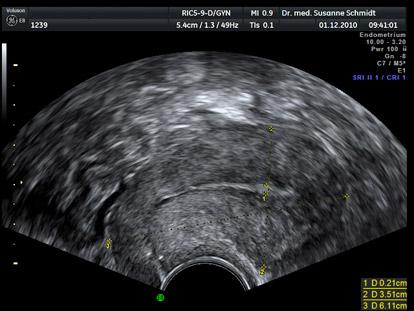

Bild zu heute ist mein erster arzt besuch - Schwanger - wer noch? Rund um die Schwangerschaft

Bissl früh für den ersten Termin,oder?Ich empfehle nicht vor der 7./8. Woche zz gehen,wenn alles ok ist.Dann sieht man auch was auf dem Ultraschall.Jetztsieht der Arzt quasi noch nix.Höchstens aufgebaute Schleimhaut und es kann immer noch jede Menge passieren Ich wünsche Dir eine tolle Schwangerschaft und falls du es noch nicht tust,nimm fleißig ein Folsäurepräparat ein. Grüße aus dem Oktoberbus 2014 Cherry mit Hendrik

Ich denke, so ein früher Arztbesuch bringt dir leider gar nix....bei mir war sogar der Test beim Arzt negativ, weil es kein frischer Morgenurin war....er hat höchstens eine hochaufgebaute Schleimhaut gesehen... Ich denke, du solltest noch 2-3 Wochen warten, bis du gehst....meistens sind die Frauen total verunsichert, wenn man noch nichts sieht. Aber ich wünsch dir das Beste für deine Schwangerschaft und noch Herzlichen Glückwunsch